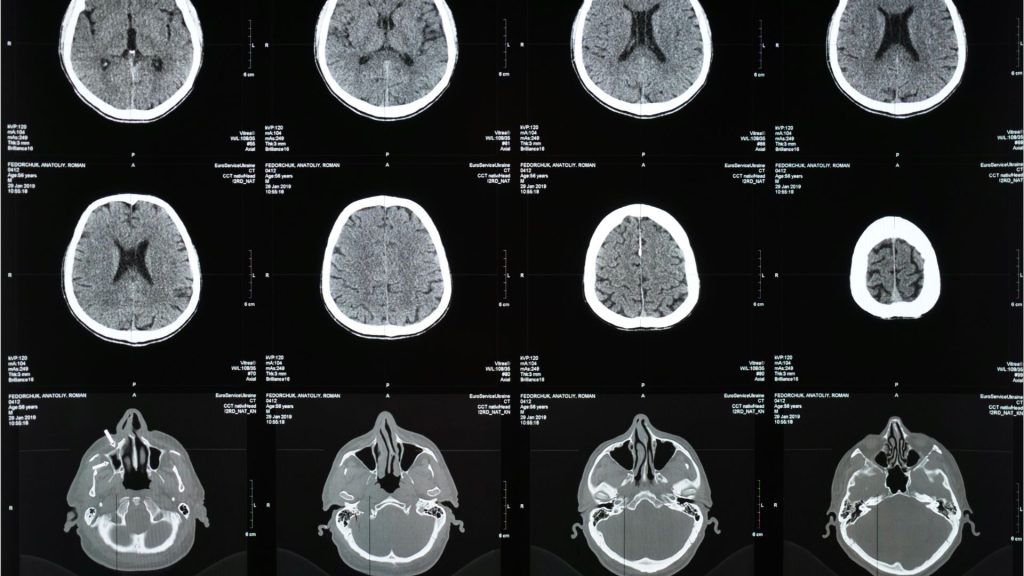

Two of the most devastating injuries one can sustain during an accident are to the brain and spinal cord.

Were you or a loved one injured in an accident and sustained a brain injury or a spinal cord injury? It is vital that you get immediate help.